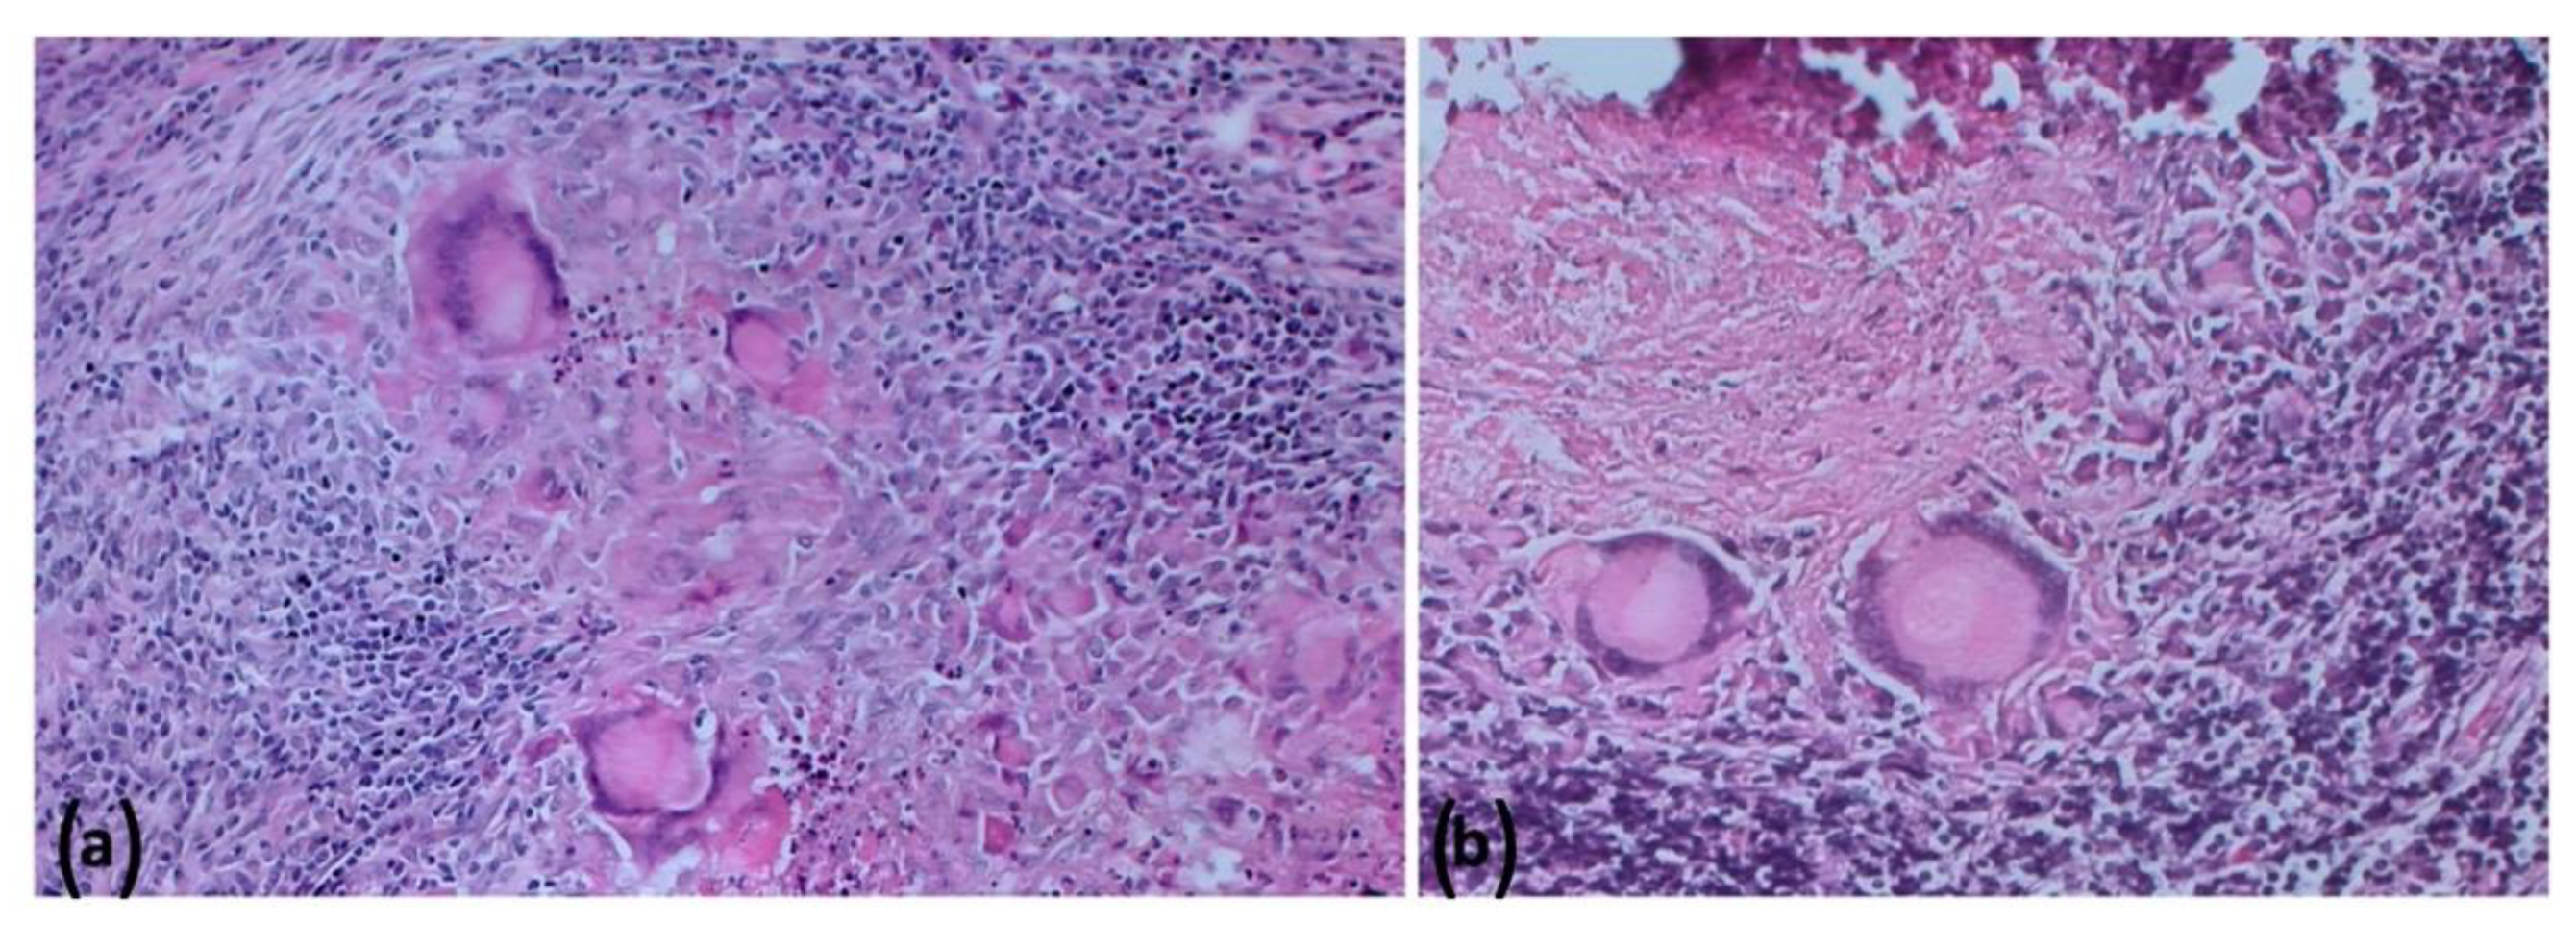

2.5. Histopathologic Findings